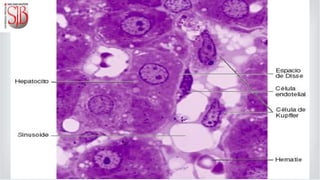

Los vasos quilíferos se unen y llegan al hígado a través de la vena hepática. Estas de

distribuyen por las venas centrales de los lobulillos hepáticos, para luego distribuirse

por los capilares sinusoidales ubicados entre las trabéculas hepáticas o de Remack.

Las moléculas pasan al espacio de Disse de donde son tomadas por los hepatocitos.

Los hepatocitos realizan la glucoronoconjugación, y finalmente se produce la bilis.

Ésta va por los capilares biliares, pasa por el espacio de Düke para desembocar en los

conductillos biliares que son visibles en los espacios interlobulillares o de Kiernan o

porta. Se observan junto a vénulas y arteriolas.

HÍGADO Los vasos quilíferosse unen y llegan al hígado a través de la vena hepática. Estas de distribuyen por las venas centrales de los lobulillos hepáticos, para luego distribuirse por los capilares sinusoidales ubicados entre las trabéculas hepáticas o de Remack. Las moléculas pasan al espacio de Disse de donde son tomadas por los hepatocitos. Los hepatocitos realizan la glucoronoconjugación, y finalmente se produce la bilis. Ésta va por los capilares biliares, pasa por el espacio de Düke para desembocar en los conductillos biliares que son visibles en los espacios interlobulillares o de Kiernan o porta. Se observan junto a vénulas y arteriolas.